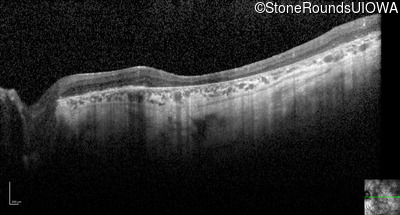

Optical Coherence Tomography - Right - 20/200 +2

Exemplar / OCT Stack